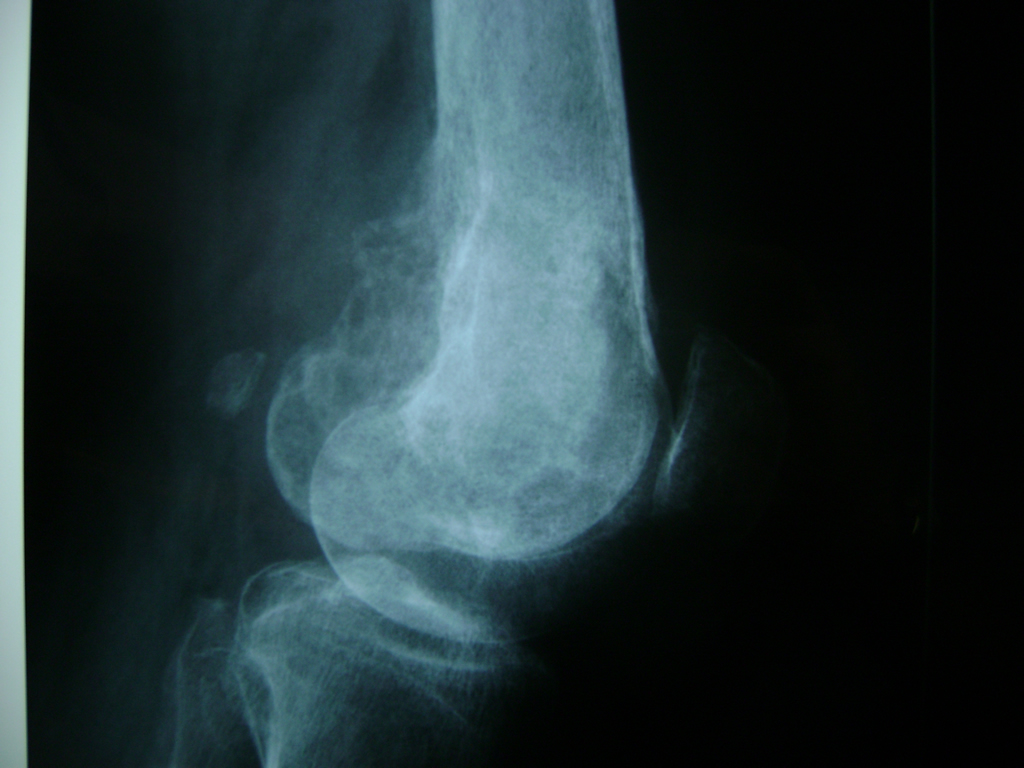

La artroscopia de rodilla es un cirugía en el cual la estructura interna de la articulación es examinada ya sea para realizar un diagnostico o para realizar un tratamiento, este procedimiento se realiza utilizando un instrumento parecido a un pequeño tubo llamado artroscopio.

La artroscopia se popularizo en 1960 y hoy en día es muy común en todo el mundo. Típicamente, es realizada por cirujanos ortopédicos de manera ambulatoria. Cuando se realiza de manera ambulatoria los pacientes pueden regresar a casa después de la operación, no se requiere quedarse en hospital.